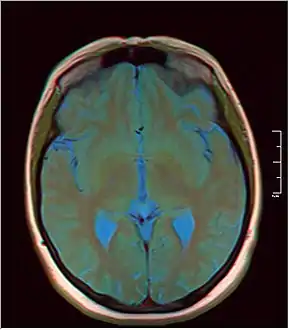

MRI axial in false color